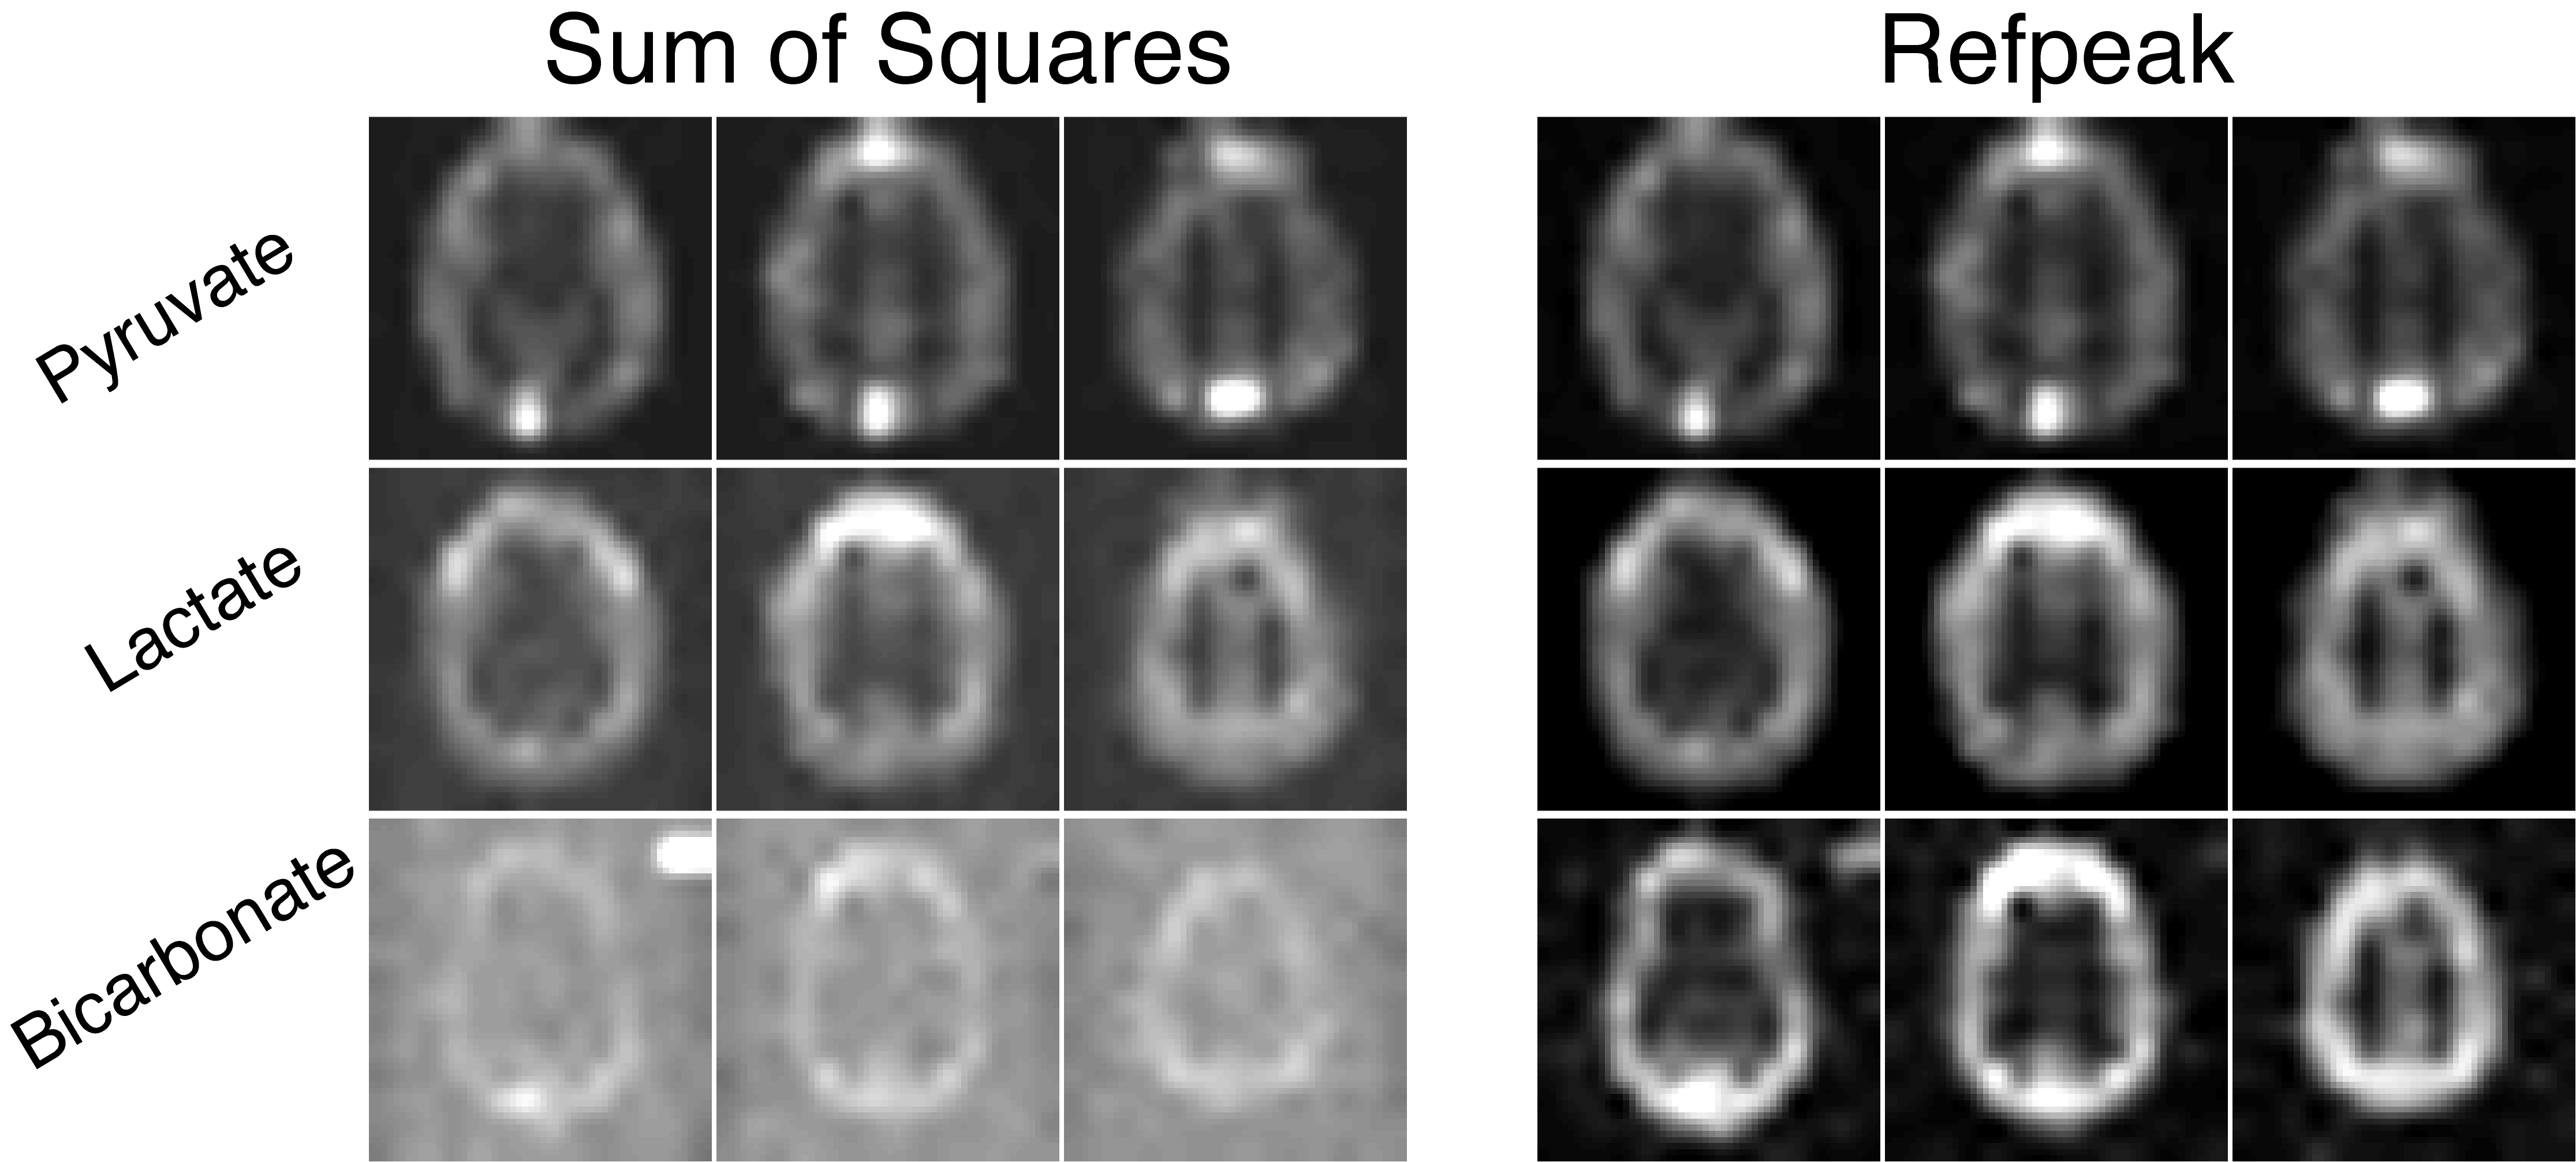

Alternatively, data-driven methods can estimate the coil sensitivities directly from the fully sampled hyperpolarized data (67,70). Coil weights are estimated from the injected substrate and then used to combine the data in a uniform noise reconstruction (71). Extracting the complex coil weights from the hyperpolarized data provides an easy and excellent approximation of the coil sensitivities while maintaining valuable phase information in the coil-combined images. A comparison between the sum-of-squares and data-driven coil combination methods (Refpeak) in a human hyperpolarized brain experiment of [1-13C]pyruvate can be seen in Fig. 9. While image quality is sufficient for the high-SNR pyruvate images using a simple sum-of-squares approach, image quality is degraded for lactate and especially bicarbonate when the coil weights are not known, reducing SNR and limiting the achievable spatial resolution. The Refpeak reconstruction has an outsized impact on the noisiest images, such as bicarbonate and late-phase pyruvate dynamics, significantly improving image quality and contrast compared to a sum of squares approach and will enable robust quantification of HP 13C metabolism.

Figure 9. Images of hyperpolarized [1-13C]pyruvate, [1-13C]lactate, and 13C-bicarboate human brain data acquired with a 32-channel coil and reconstructed with a sum-of-squares or data-driven (Refpeak) approach. While image quality is sufficient for the high-SNR pyruvate images using a simple sum-of-squares coil combination, image quality and SNR is degraded for lactate and especially bicarbonate when the coil weights are not known, limiting the achievable spatial resolution.